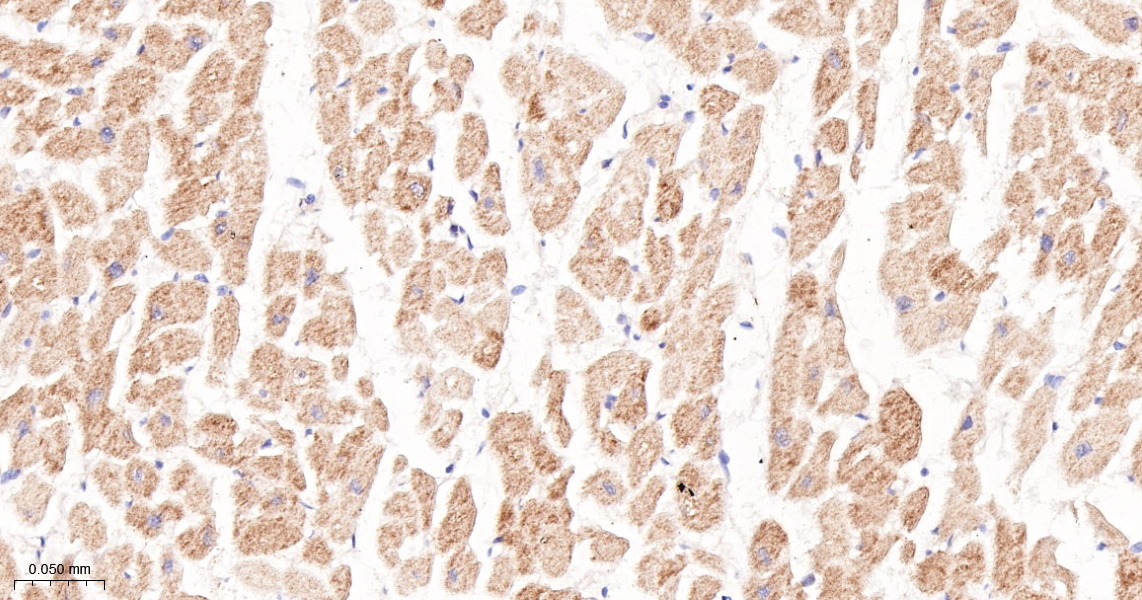

phospho-RAF1 (Ser259) Recombinant Antibody

Product Name phospho-RAF1 (Ser259) Recombinant Antibody

Applications WB, IHC-P, IHC-F, IF

Reactivity Human, Mouse, Rat

IHC-P 1:200-400